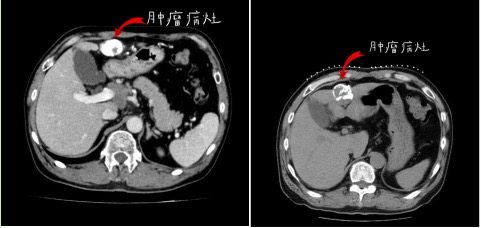

患者术前CT

粒子植入术中定位

粒子植入手术术中穿刺